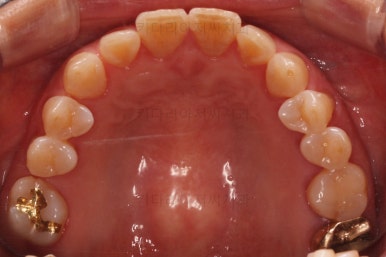

초진 때의 사진입니다.

전반적으로 치열이 삐뚤하고 불균일한 양상이긴 하지만 꼭 이런 부분들까지 교정을 해야 하는 건 아니에요.

치열에 대한 본인의 개선 의사가 있다면 전반적인 교정을 해줄 필요가 있지만 그렇지 않다면 굳이 할 필요가 없는거죠.